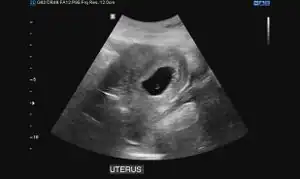

Ultrasound

Obstetric ultrasonography may also be used to detect and diagnose pregnancy. It is very common to have a positive at home urine pregnancy test before an ultrasound. Both abdominal and vaginal ultrasound may be used, but vaginal ultrasound allows for earlier visualization of the pregnancy. With obstetric ultrasonography the gestational sac (intrauterine fluid collection) can be visualized at 4.5 to 5 weeks gestation, the yolk sac at 5 to 6 weeks gestation, and fetal pole at 5.5 to 6 weeks gestation. Ultrasound is used to diagnose multiple gestation.[3][19]